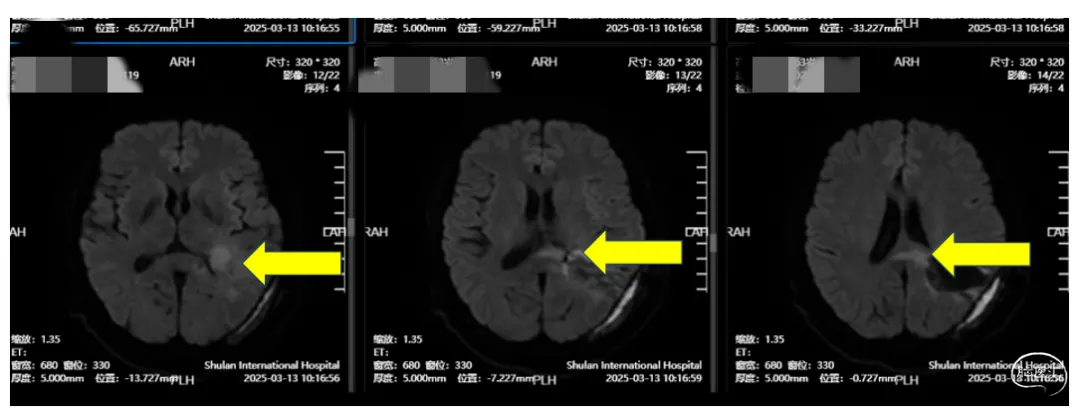

2月初,高女士因记忆力下降,思维迟缓和四肢无力就诊于山东某知名三甲大医院。进行PET-CT+颅脑MRT检查,提示“左顶叶、胼胝体占位性病变”。一场紧急手术切除了肿瘤,但术后病理报告却让其家属心中一沉——“胶质母细胞瘤”,这是恶性程度最高、侵袭性最强的脑肿瘤之一。

(图1:术前:左顶)